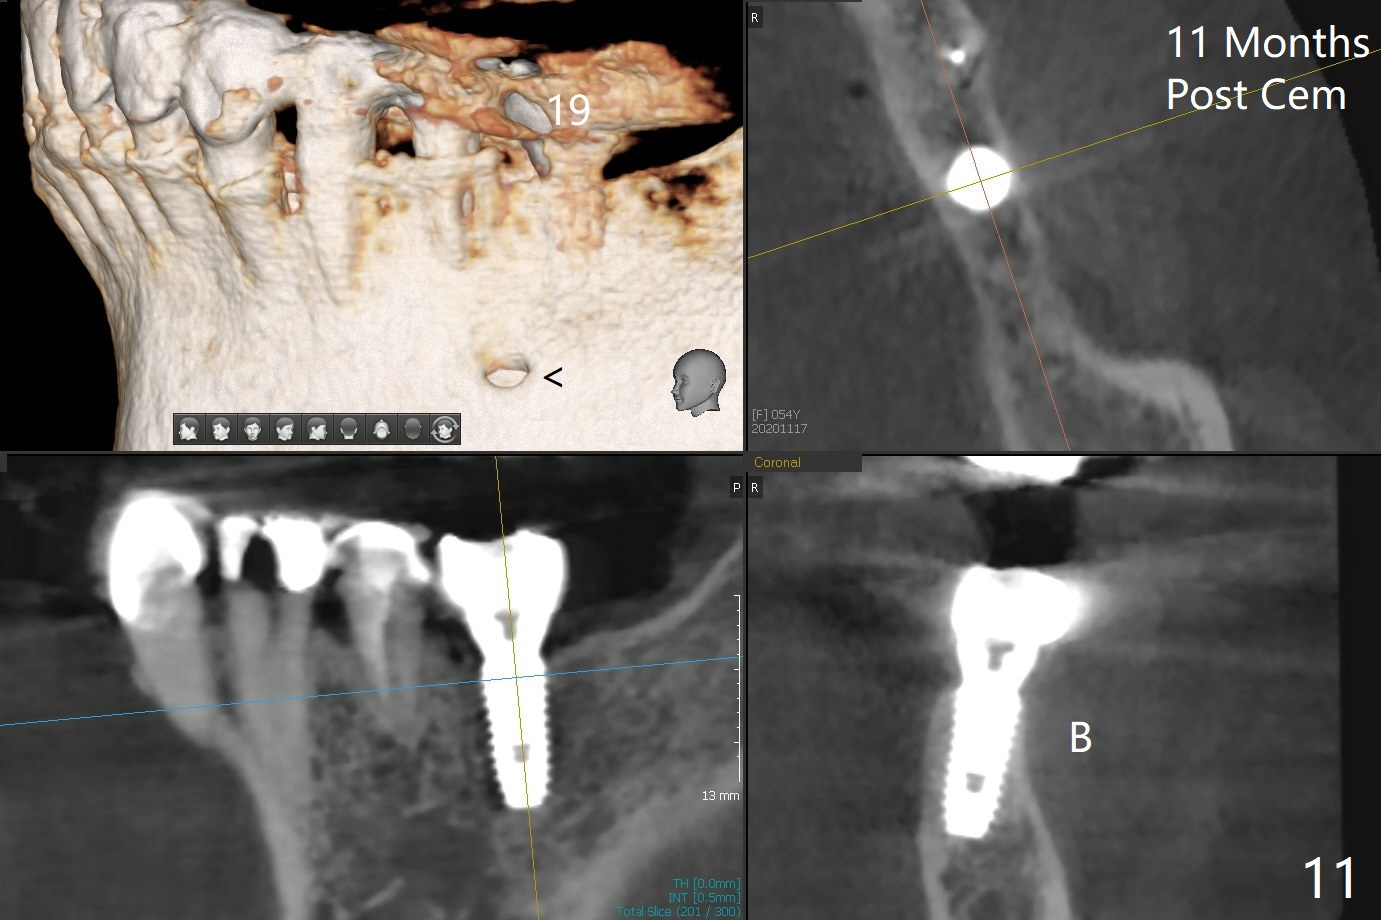

The buccal plate is present, although thin 11 months post cementation (Fig.11).